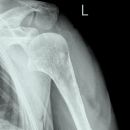

Schwedenstatus (3 Aufnahmen)

1. Aufnahme:

Patient steht mit dem Rücken am Stativ, gesunde Seite mit 45° Keil angehoben, Arm und Ellenbogen um 90° angewinkelt, Handinnenfläche am Körper angelegt. (Innenrotation)

2. Aufnahme:

Gleiche Stellung des Patienten, jedoch Unterarm nach vorne drehen (Neutralstellung), d.h. 45° zum Stativ, Arm zeigt in Richtung Fußspitze.

3. Aufnahme:

Patient steht mit flach angelegtem Schulterblatt am Stativ, Oberarm 90° abduziert und maximal nach außen rotiert, Ellenbogen um 90° gebeugt (Daumen zeigt zum Stativ), wie 2. Ebene der Schulter in der Medizin, Kopf zur gesunden Seite drehen.

1. und 2. Aufnahme:

Trifft 15-20° cranio-caudal auf Oberarmkopf.

Senkrecht auf Oberarmkopf. Oberer Kassettenrand: 2 Querfinger oberhalb der Hautgrenze.

Indikation

Bei Verdacht auf Fraktur des Tuberculum major, nach Luxation und Periathritis, bei Impressionsfraktur nach Luxation, was bei normalen Schulteraufnahmen nicht diagnostizierbar sind.

Qualitätskriterien

Freie Darstellung des Gelenkspaltes.

1. Aufnahme: Tuberculum majus und minus nebeneinander dargestellt.

2. Aufnahme: Besonders deutlich kommt hier die obere Facette des Tuberculum majus zur Darstellung.

3. Aufnahme: Nahezu überlagerungsfreie Darstellung des Humeruskopfes und Durchblick durch das Humeroglenoidalgelenk.